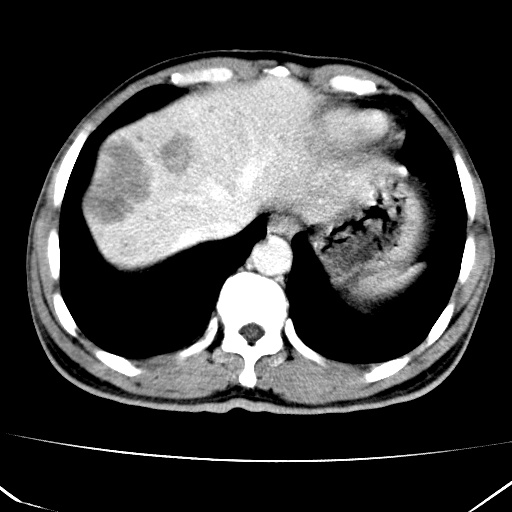

标题: CT17975:请求会诊。男、57岁。上腹部胀痛2天。临床诊断:糜 [打印本页]

标题: CT17975:请求会诊。男、57岁。上腹部胀痛2天。临床诊断:糜

肝脏多发类圆形低密度影,考虑肝脏转移瘤,肝胃韧带一淋巴结肿大,原发?胃癌?

考虑胃癌并肝脏及腹膜后淋巴结转移;不排除淋巴瘤。

肝内转移瘤,腹腔及腹膜后淋巴结转移。